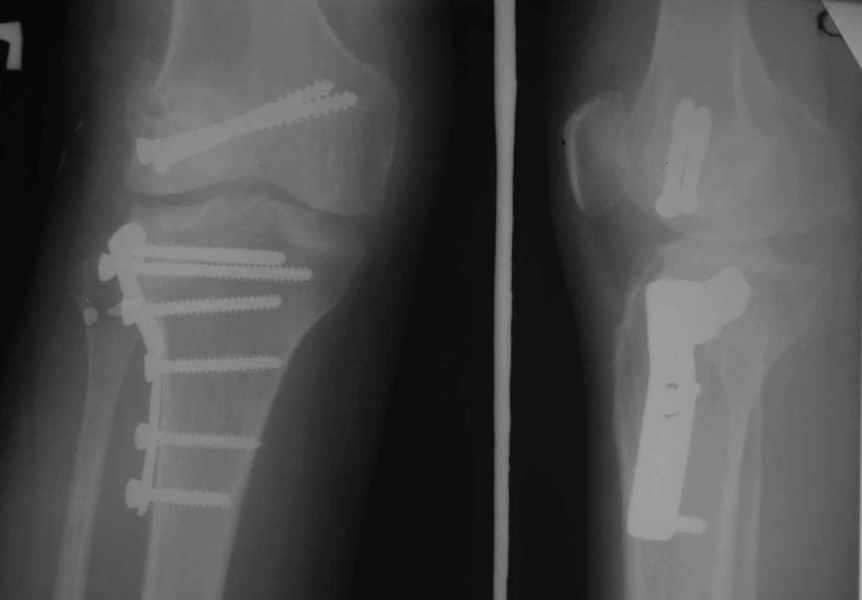

Как вариант решения прогрессирующей вальгусной деформации коленного сустава я бы предложил косую остеотомию дистального отдела бедра с фиксацией пластиной и компрессирующим винтом.

Взгляните на снимки , может быть это вам поможет.

Около 5 лет применяю этот тип дистальной остеотомии бедра для коррекции механической оси Н/К ( более 20 случаев) - достаточно эффективная операция.

Уважаемый Евгений ! Спасибо за ответ, но мне представляется, что в нашем случае основной проблемой является не столько прогрессирующий вальгус конечности, сколько несросшийся перелом мыщелка бедра и дефект мыщелка большеберцой кости - вероятно первичная репозиция выполнялась без пластики.

На своем горьком опыте убедился, что синтезировать мыщелковые импрессионные внутрисуставные переломы б\б кости без костной пластики - дело неблагодарное, рецидивируе деформация, мыщелок всегда *проваливается*. Чистые split type переломы можно ограничиваться и одной только межфрагментарной компрессией.

Может стоит сначала добиться сращения наружного мыщелка бедра( костная пластика) и коррекции оси?

Мне представляется, что прогрессирующий вальгус и обусловлен несросшимся переломом мыщелка бедра (томограммы -зона межфрагментарного склерозирования), а циклические нагрузки на сустав во время ходьбы усугубляют ситуацию. Как вы думаете, в этой ситуации насколько вероятен риск развития аваскулярного некроза мыщелка бедра?

Относительно "рубцовой подушки" я имел в виду остатки мениска ( частично вколоченного в дефект мыщелка и фрагменты хряща), все таки на рентгенограммах суставная щель в этом отделе чем то заполнена. Что касается некроза мыщелка бедра, то мне кажется он уже наступил - томограмма ноябрь5.

С учетом всего сказанного - наличия прогессирующего вальгуса конечности, довольно приличного объема движений, имеющегося, вероятно, некроза мыщелка бедра, наиболее рациональным представляется удалить пластину с б\б кости, произвести остеотомию б\б кости с коррекцией вальгуса, разгрузив тем самым наружный отдел сустава, и синтезировать фрагменты голени накостным фиксатором. Максимально тано начать восстановление движений в суставе. Скорее всего рано или поздно речь о протезировании всеже возникнет, но мы хотя бы будем иметь приличную ось конечности.

Тут ситуация совсем другая. Деформация не около-, а самая что ни на есть внутрисуставная. Покорректировать внешний вид конечности путем остеотомии дистального отдела бедра и high tibia (плюс или минус клин, одномоментно-постепенно, аппарат-пластина-стержень - дело третье) не сильно сложно, но это не решение проблемы. У больной, по

сути отсуствует латеральный отдел коленного сустава, что требует костно-пластических вмешательств непосредственно на артикулирующих

поверхностях.

Может быть, целесообразней сразу протез, чем тот же протез, но после сложных, но сомнительно результативных операций типа замещения алломыщелком, моделирующих резекций и т.п.? Ну и в любом случае движения лучше бы разработать получше до любой операции.